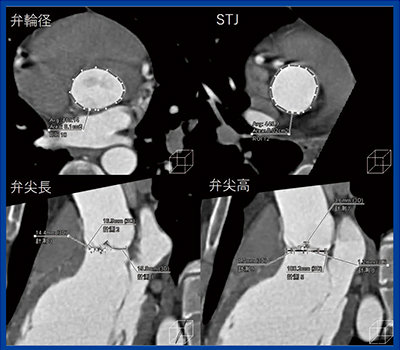

大動脈弁狭窄は,大動脈弁が狭窄し弁が開放されなくなる状態で,左室に圧負荷がかかり,駆出が正常に行われなくなり心不全を起こす。大動脈弁狭窄に対しては,10年以上前から経カテーテル的大動脈弁置換術(TAVI)が行われ広く普及している。心臓CTで弁輪径,弁栓の長さ,高さなどを計測して,留置する弁径の選択など術前のプランニングを立てることが重要である(図3)。

図3 大動脈弁狭窄での「TAVR術前プランニング」による解析

大動脈弁逆流は,大動脈弁が閉鎖不全を起こし,拡張期に逆流を生じる状態で,左室の容量負荷から心不全を起こす。術前のCTでは,弁尖の形態,弁尖の長さ,大動脈基部の評価などを行う。人工のグラフトを留置する手術を行う可能性が高いので,大動脈基部の計測と弁輪径,STJを計測してデバイスを決定することが重要である。図5は,二尖弁で右冠尖が逸脱している症例だが,弁尖の長さ,高さを含めて計測し,人工グラフトの中に自身の弁を縫い付ける“Reimplantation”という手術を行い,良好な結果を得た。

図5 大動脈弁逆流症例の大動脈基部,弁尖長,弁尖高の計測